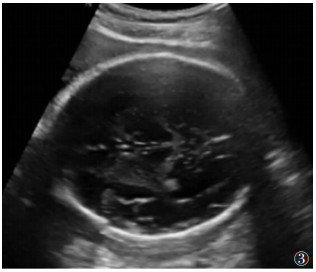

使用Philips EPIQ5彩色多普勒超声,在丘脑水平的横断位图像上及脉络丛后缘水平垂直于侧脑室的直线上测量侧脑室。仅测量位于最深半球的侧脑室[7]图 3)。

图 3 胎儿头颅超声成像的轴面,测量侧脑室的直径